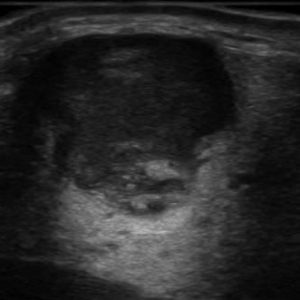

Viêm tuyến nước bọt

Lượt xem: 168» 16-01-2021 -

Viêm tuyến nước bọt

Lượt xem: 173» 16-01-2021